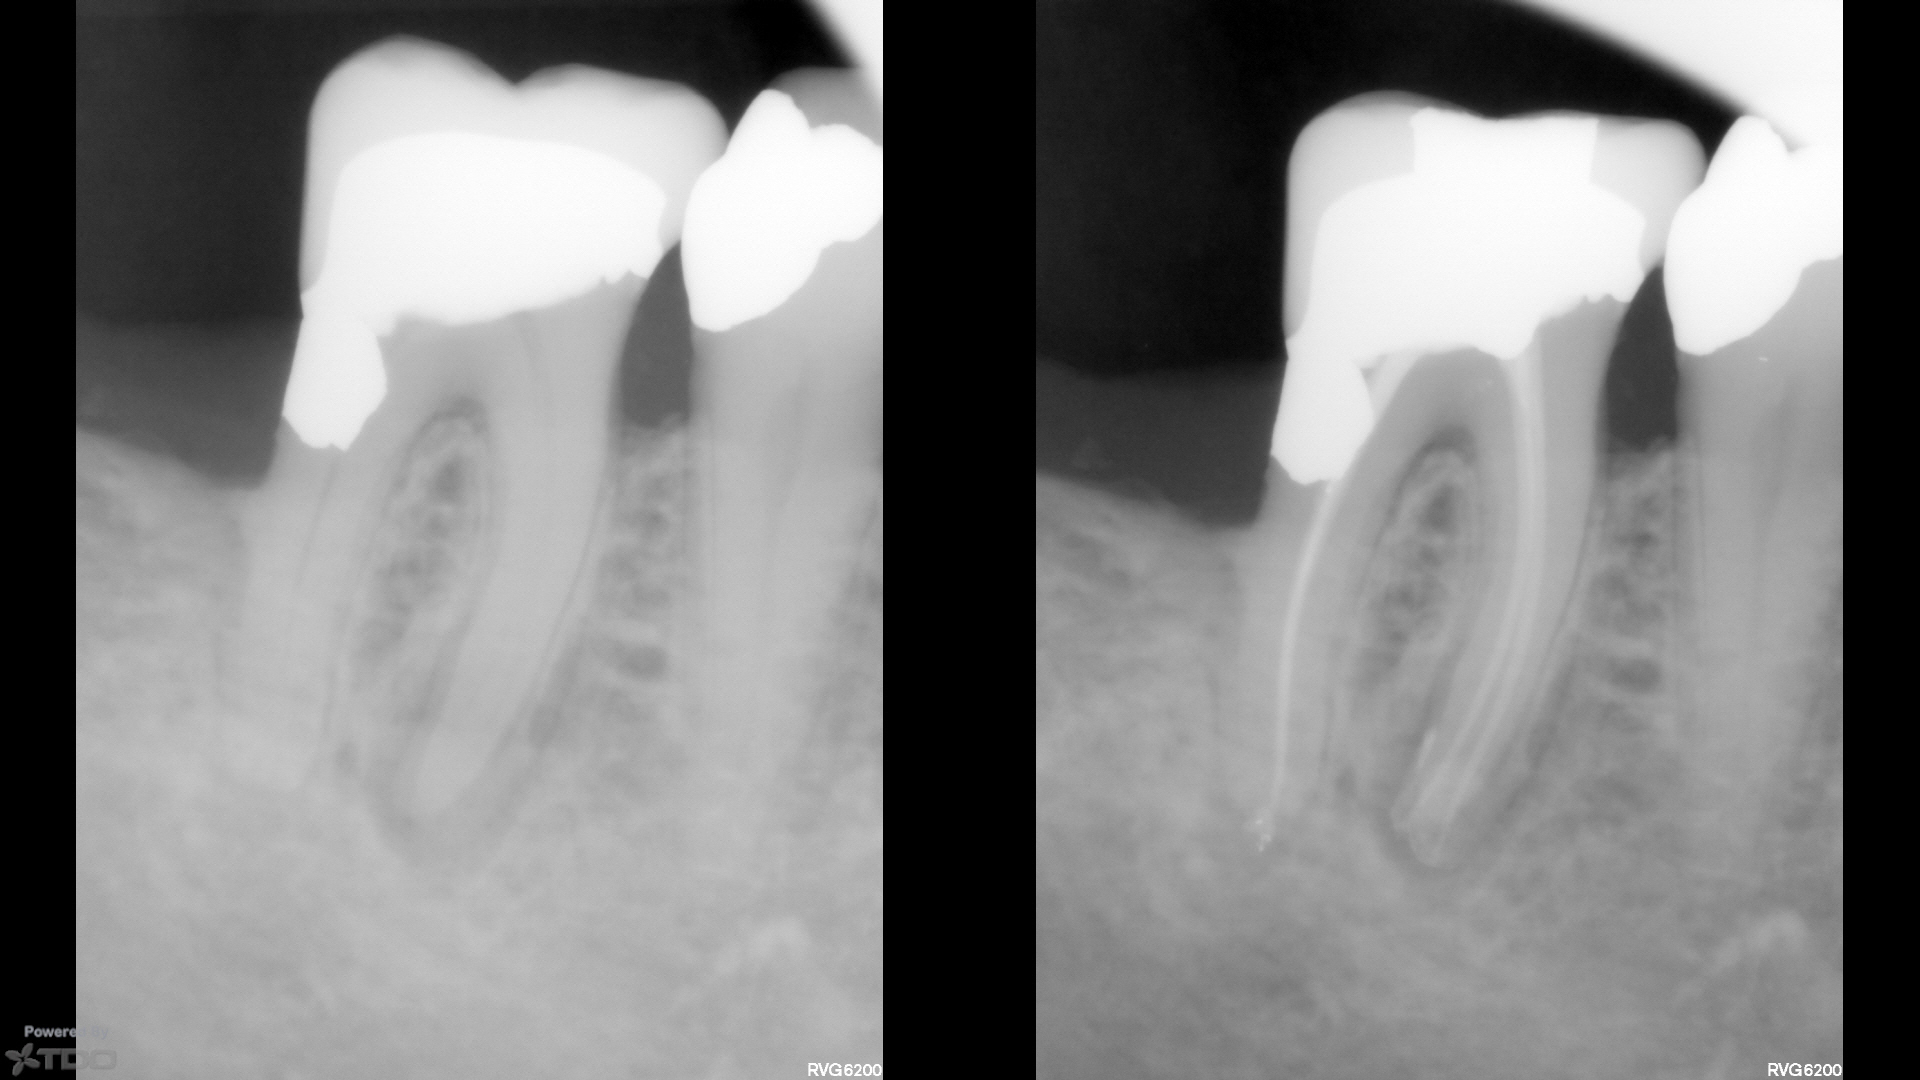

Here are a couple of single-cone BC sealer cases from today, and last week.

Both are SSW 17/V.04, single-cone (#20 cone…very thin and flimsy).

No downpack, no backfill.

CBCT post-op on the one from today demonstrating some apical anatomy if that tickles your fancy.